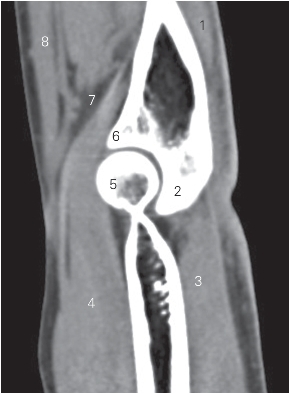

图4-30 经肘关节的矢状断层CT图像(软组织窗)

1 指深屈肌 flexor digitorum profundus 2 尺骨鹰嘴 ulnar olecranon

3 肱三头肌和肌腱 triceps brachii and tendon

4 肱肌 brachialis 5 肱骨滑车 trochlea of humerus

6 尺骨冠突 ulnar coronoid process 7 肱动脉 brachial artery

8 旋前圆肌 pronator teres